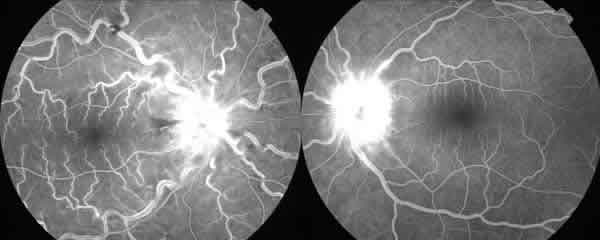

Varón de 21 años que acude a urgencias por visión borrosa intermitente de unos 20 seg. de duración en ojo derecho (OD) desde hace 15 días, con sensación de nube constante los últimos 5 días. Es fumador de 20 cigarrillos al día y está en tratamiento con doxiciclina para el acné. En la exploración oftalmológica la agudeza visual (AV) era de 0.150 en OD y de la unidad en el ojo izquierdo (OI) sin DPAR en ninguno de ellos. En la biomicroscopía anterior (BMA) se observaban células de intensidad ++ en OD y de + en OI con precipitados endoteliales finos y escasos en ambos ojos (AO). La tensión ocular era de 10 en AO. En el fondo de ojo (FO) existía un edema de papila bilateral con congestión y tortuosidad vascular más llamativa en el OD con alguna hemorragia y exudados (fig. 1). En la angiofluoresceingrafía (AFG) aparecía una hiperfluorescencia en ambas papilas y en grandes venas del OD y en la angiografía con verde indocianina (ICG) no se observaban focos de coriorretinitis (figs. 2 y 3). El test de colores era normal en AO y el TAC cerebral sin hallazgos. Se instaura tratamiento tópico con corticoides, antibióticos y midriáticos y a los 2 días la AV baja en OD a 0.05 observándose un importante edema macular (fig. 4). El estudio complementario con Rx de Tórax, analítica para descartar patología infecciosa (Borrelia, Bartonella, Treponema P, etc.) e inmunitaria con batería completa de uveitis así como Ac Antifosfolípidos y pruebas de coagulación, glucemia, lípidos etc., fue negativo excepto la elevación del ASLO y el HLA B5 +. El estudio neurológico descartó un «pseudotumor cerebri» que pudiera estar en relación con la toma de tetraciclinas. La RMN craneal descarta asimismo la trombosis de los senos venosos y la existencia de enfermedades desmielinizantes.

Fig. 2. Angiografía fluoresceínica que muestra dilatación y tortuosidad en grandes vasos en el OD y edema papilar en OI.

Fig. 3. Angiografía con verde de indocianina sin focos de coriorretinitis.